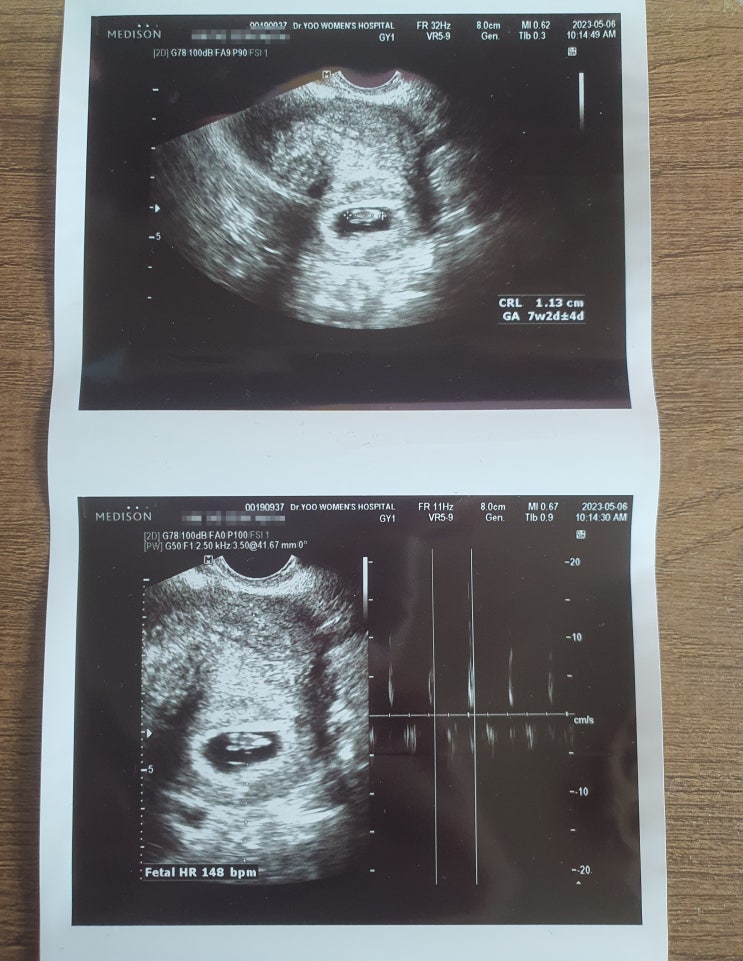

임신 12주 태아 크기 1차 기형아 검사 입덧 이야기

한 달 전만 해도 젤리 곰 같았던 우리 신이는 무럭무럭 자라 드디어 손가락 발가락 그리고 척추뼈까지 다 ...

임신 초기 증상 울렁거림 변비 매일 체한 것 같은 기분

사람마다 임신 초기 증상이 모두 다르기 때문에 무엇이 맞는다고 할 수는 없지만 그래도 몇 가지의 공통점...

임신 6주 차 7주 차 미리 준비해야 될 것들

안정기에 찾아들면 말 그대로 안정기라 걱정 할 것이 없다고 생각을 했는데 오히려 걱정거리만 더 늘어가는...

임신 초기 증상 4주 차 5주 차 기록

원래 결혼하고 난 후 1년 정도 신혼 생활을 가지고 아기를 가지자고 결심을 했으나 생각처럼 임신은 잘 안...